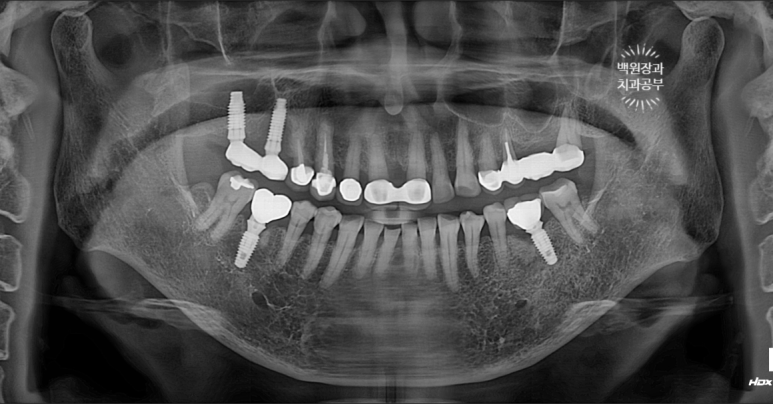

약 20년 전에 제작한 오른쪽 위 외산 임플란트에서 고름이 나온다는 주소로 내원한 70대 여자 환자분이었습니다.

임플란트는 아마도(?) 브레네막(Branemark) 임플란트로 생각되는데, 당시에는 최고의 명품이었죠.

여튼, 좋지 위치에 식립되어 있는 임플란트도 아니었고, 임플란트 주위염이 심하여 농이 나오는 상태였기 때문에 임플란트를 제거하기로 하였습니다.

또 다른 이유로 잘못 식립된 임플란트의 위치 때문에, abutment(=지대주)가 너무 짧아 임플란트 크라운이 자주 탈락하는 상태였어요. 기둥이 두껍고 길어야 보철물이 잘 붙어있을텐데 말이죠...?

이렇게 가늘고 짧은 기성 어버트먼트로 보철물을 만들면, 잦은 임플란트 크라운 탈락에 시달리게 됩니다...

잦은 임플란트 크라운 탈락은 임플란트 주위염을 야기하고.. 결국 임플란트 재수술을 하게 되지요..

오른쪽 위 임플란트 2개를 제거하고, 뼈이식을 하였습니다.

임플란트를 제거하고 다시 임플란트를 새로 식립할 계획이었기 때문에, 뼈이식을 함께 해드리기로 계획하였어요.

오전의 임플란트 4개 제거에 이어, 오후에 임플란트 2개를 추가로 제거하였습니다....

보다 짧은 임플란트를 보시면, 주변에 뿌옆게 건전한 잇몸뼈와 함께 제거했다는 것을 보실 수 있을거에요..

덴티움 trephine bur KIT를 이용하여 제거하였습니다!!

수술 후 찍은 치과용 파노라마 엑스레이를 보시면,

임플란트가 사라진 자리에 충분히 자리잡은 뼈이식재를 보실 수 있을거에요!